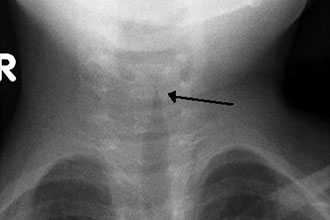

Обратный поток ( гастроэзофагеальный рефлюкс Гастроэзофагеальная рефлюксная болезнь (ГЭРБ) При гастроэзофагеальном рефлюксе содержимое желудка, включая кислоту и желчь, проникает из желудка назад в пищевод, вызывая воспаление в пищеводе и боль в нижней части грудной полости. Рефлюкс. Прочитайте дополнительные сведенияЭндотрахеальная интубация (процедура введения пластиковой дыхательной трубки в дыхательное горло [трахею] через рот или нос, проводимая, например, во время общей анестезии) может стать причиной появления контактных язв голосовых связок, в случае если дыхательная трубка слишком велика.

Симптомы включают легкую боль во время разговора или при глотании и сиплость голоса различной степени.

Диагностика контактных язв голосовых связок

Врач ставит диагноз контактных язв голосовых связок по результатам осмотра голосовых связок с помощью тонкого гибкого зонда с оптической системой (ларингоскопия).

Иногда врач берет небольшой кусочек ткани для микроскопического исследования (биопсия), чтобы исключить раковую (злокачественную) природу язвочек и убедиться, что они не вызваны туберкулезом.